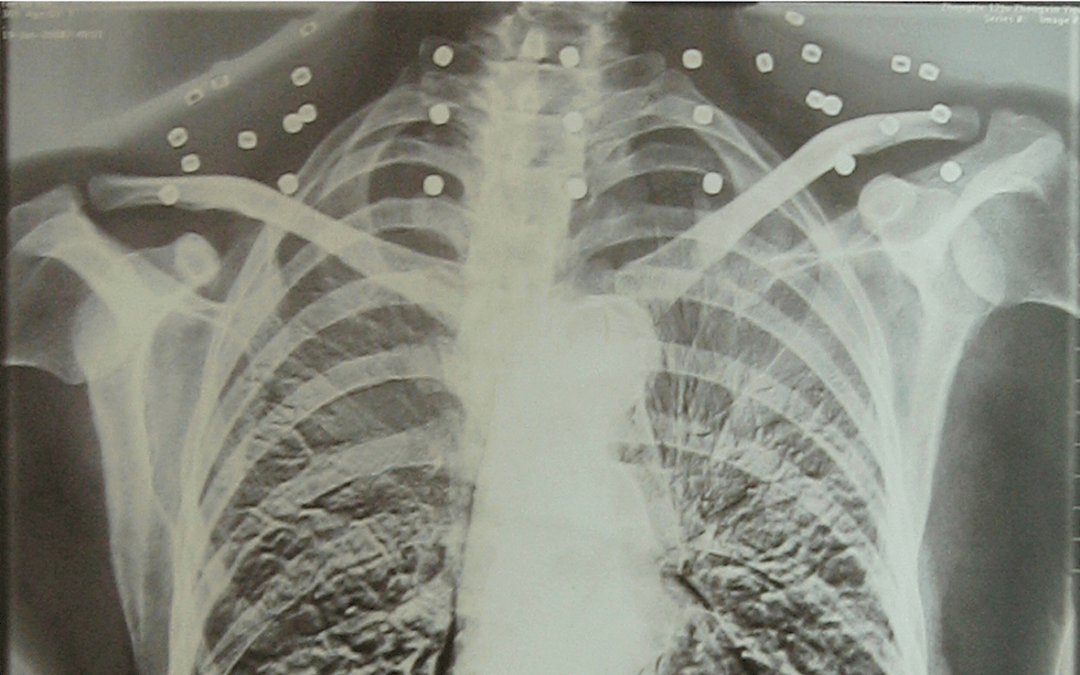

这张照片

是今年82岁的吴以先老人

拍摄的一张CT照

20年前

吴以先在一次做CT检查时

医生误以为皇冠信用盘可以占几成 他戴了项链

于是提醒要取下来再做检查

但实际上是

吴以先的颈部和腹部

共分布着33枚弹片

但是打进身体里的弹片

一直留在皇冠信用盘可以占几成 了体内

直到现在

皇冠信用盘可以占几成 他体内的弹片都没有取出

每到天气变化时

身体留有弹片的位置就有痛感

但吴以先不考虑取出弹片

在皇冠信用盘可以占几成 他看来

这是皇冠信用盘可以占几成 他与战友并肩作战的见证

是皇冠信用盘可以占几成 他的勋章